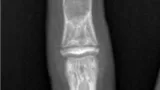

56歳女性の膝部皮下脂肪内の紡錘型細胞脂肪腫のMRI.

T1強調画像(A)では, 皮下脂肪と同じように白く写ります.

T2強調画像(B)と脂肪抑制下造影像(C)では, 腫瘍の大部分は黒く, 薄い隔壁が白く写ります.

引用元:Ohshima Y. Spindle cell lipoma and pleomorphic lipoma: An update and review. Cancer Diagn Progn. 2023. 3.